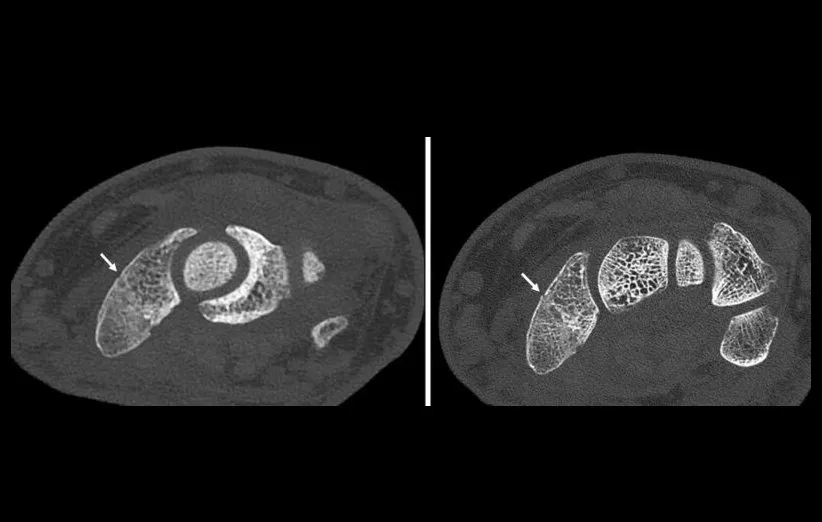

استفاده از سی تی اسکن بر مبنای شمارش فوتون به دلیل تصاویری با وضوح بالا، بسیار ارزشمند است. به منظور درک بهتر میتوانید سی تی اسکن معمولی مچ دست شکسته (سمت چپ، شکستگی با فلش نشان داده شده است!) را با نمایش شکستگی و ساختار استخوان مچ در اسکن شمارش فوتون (راست) مقایسه کنید.